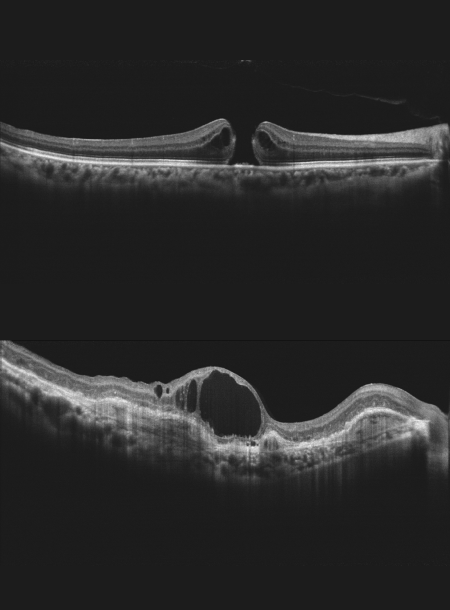

• Висока якість ОКТ-зображення

• Глибина сканування 3 мм показує деталізоване зображення склоподібного тіла, сітківки та судинної оболонки

Режим глибокої судинної томографії (DCI)

Використання глибокої судинної томографії для виявлення неоваскуляризації судинної оболонки.

High quality OCT image

Spectral domain OCT

Super luminescent diode (SLD), 840 nm